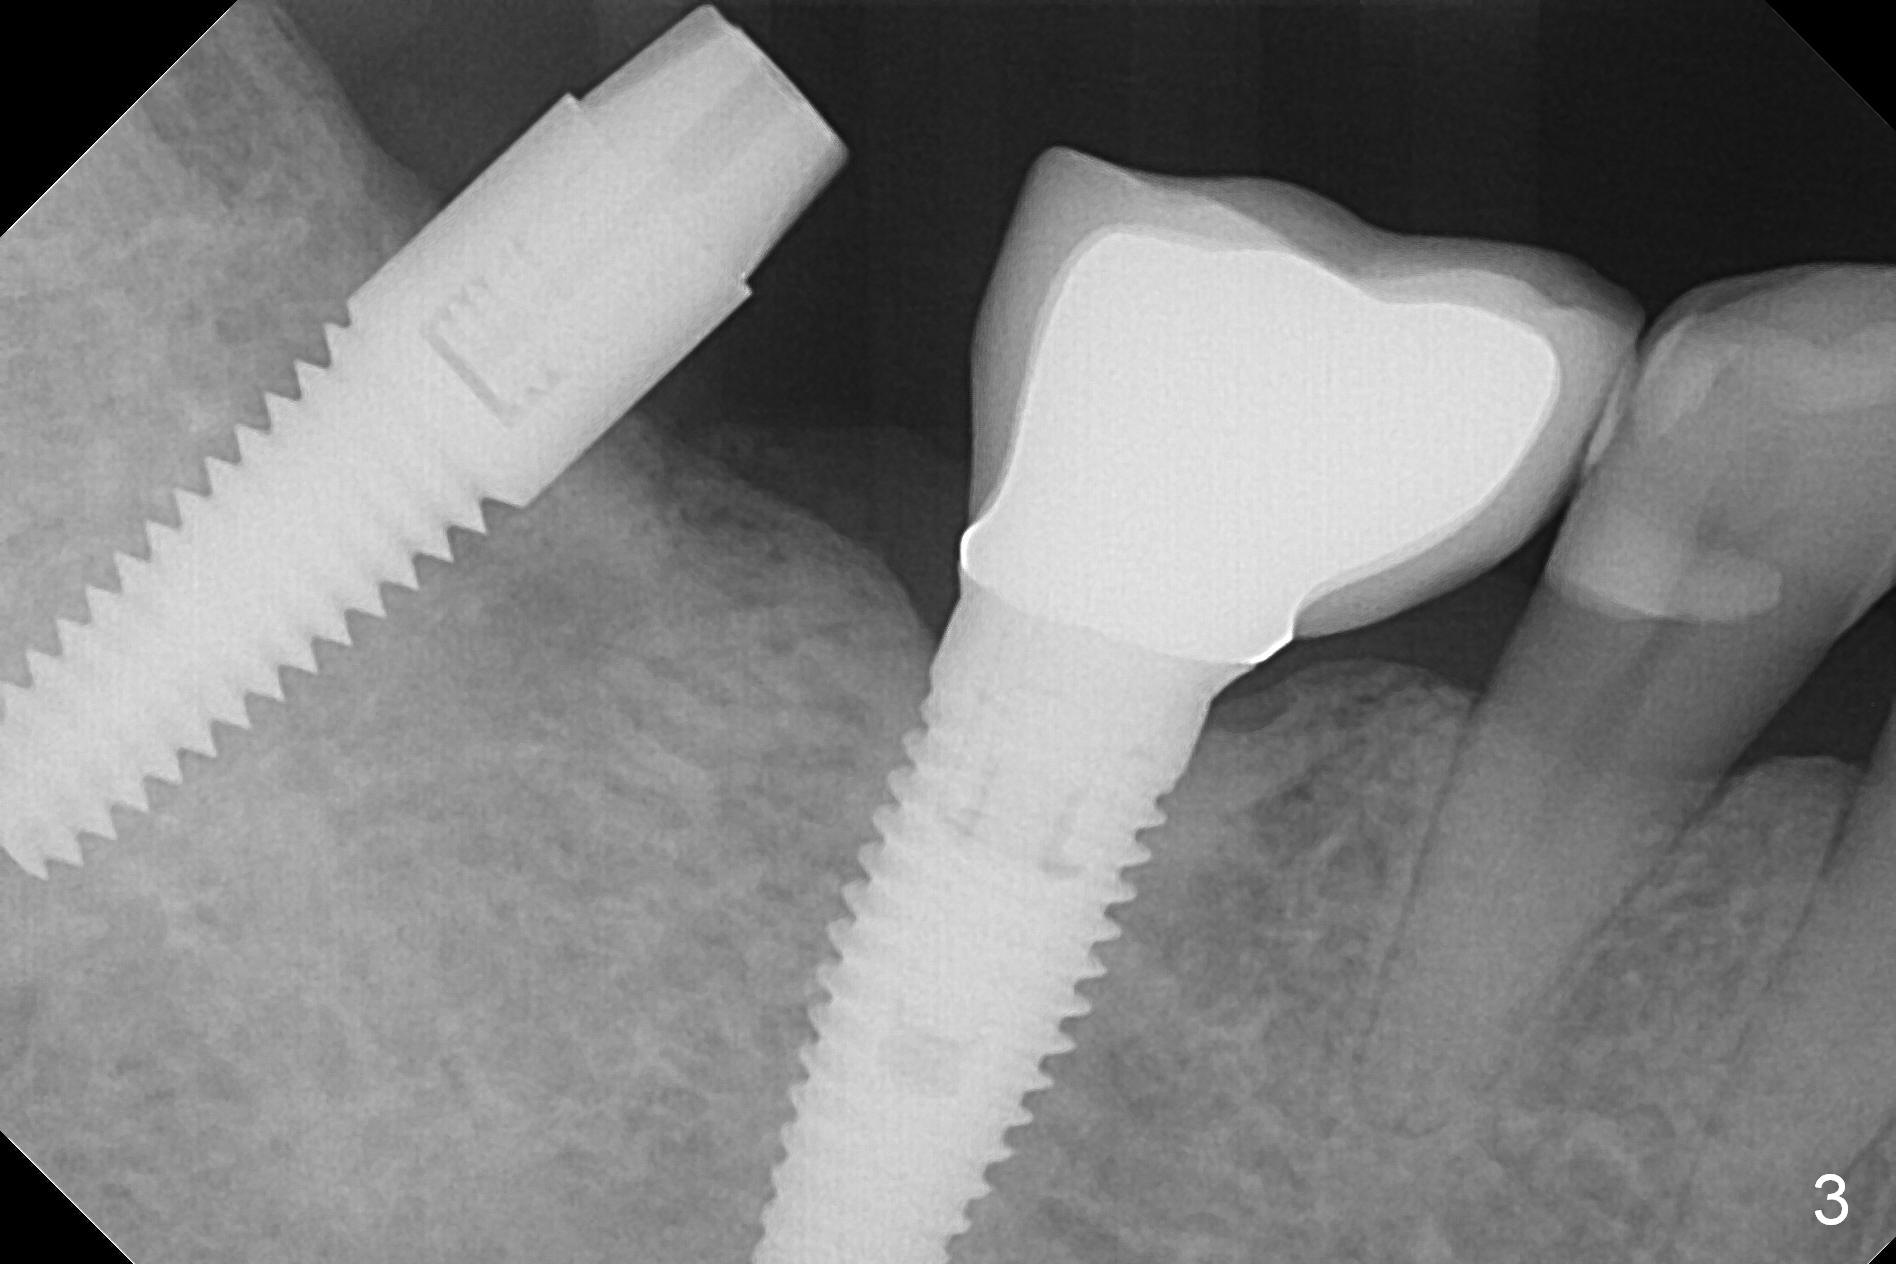

Initial osteotomy at the site of #31 using 2 mm pilot drill for 11 mm appears to be distal by 2-3 mm (Fig.1, Fig.10 A (circle, occlusal view of the edentulous and dentate (#29 and 30) areas)). Lindamann bur is used to move the osteotomy (Fig.8 white rectangle, Fig.10 B). It seems that the osteotomy returns distal as the osteotomy increases (Fig.2 (5x17 mm tap), Fig.8 arrow, Fig.10 C (green circle)). It appears to be late to change; a 5x17 mm tissue-level implant is placed with > 60 Ncm (Fig.3-5). The buccal and lingual rough surface of the implant (Fig.5 *) is covered by autogenous bone/Osteogen and Collagen Dressing (Fig.6 *). After suturing (Fig.7), periodontal dressing is applied around the abutment (Fig.5 A (4.5x3 mm)).